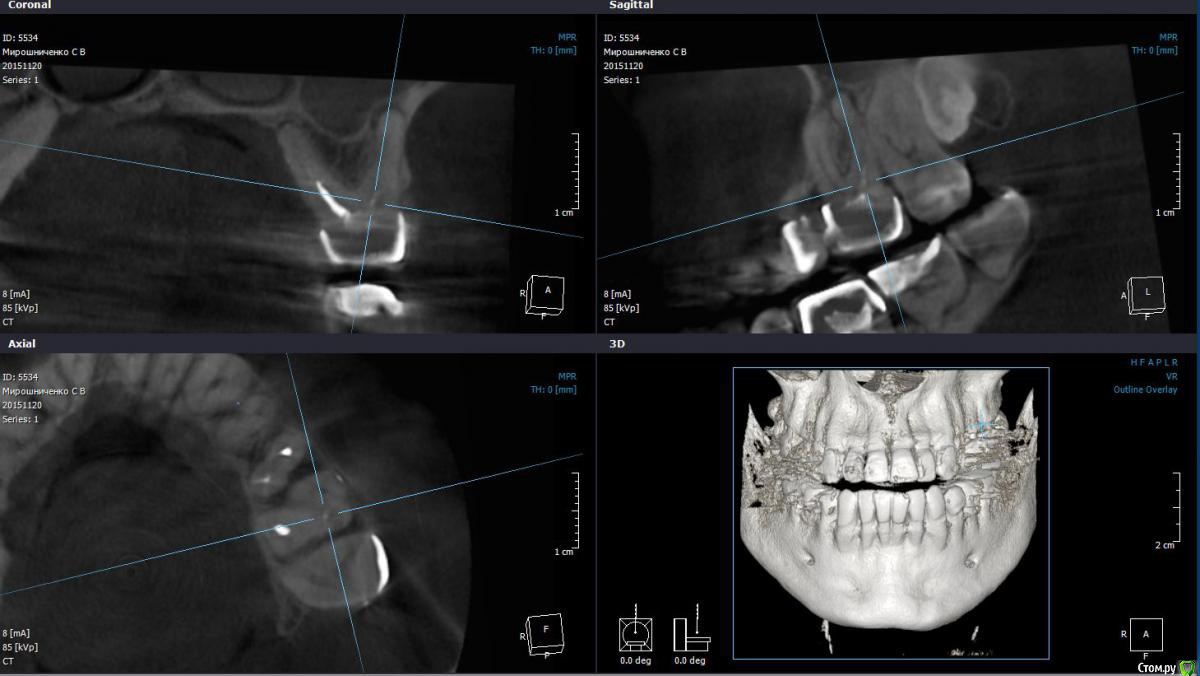

St. Опубликовано 13 июля, 2016 Автор Поделиться Опубликовано 13 июля, 2016 Асимптоматический периодонтит 35з. И случайная находка - трехканальный 34. Даж не знаю, хотела бы я такой полечить или нет) 1 Ссылка на комментарий